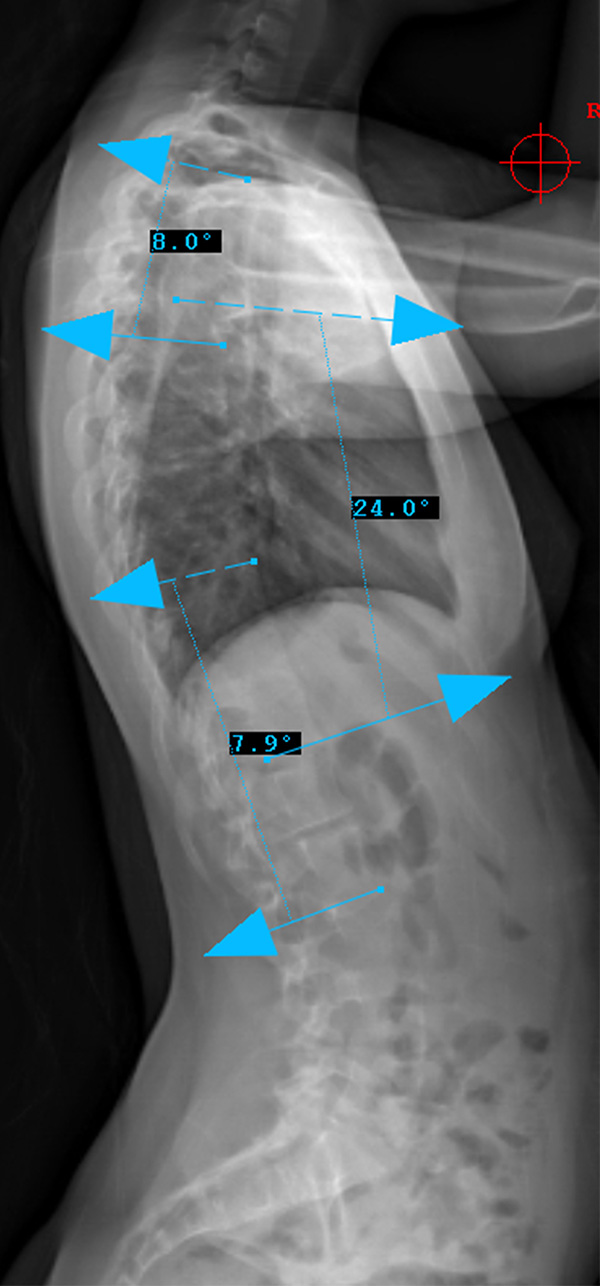

Preop LAT View

Sagittal Modifier N

T5-T12 in the 10-40o range

Therefore, Classification is Type 5CN

Lenke Type V describes a major curve in the thoracolumbar/lumbar region. The apex of the greatest coronal plane deformity is between T12 and L4. The main thoracic curve is non-structural with a side-bending Cobb of less than 25 degrees and a T10-L2 kyphosis of less than 20 degrees. All of these curves have a “C” lumbar spine modifier. The three sagittal modifiers are still applicable. These curves may be treated with either an anterior or posterior spinal fusion. The fusion levels are often the upper and lower end-vertebrae of the coronal plane deformity. For successful selective fusion of the thoracolumbar/lumbar spine the Cobb angle, apical vertebral translation, and apical vertebral rotation ratios (ThL/L:MT) should be greater than 1.25. In addition the MT curve should be flexible without evidence of thoracolumbar junctional kyphosis (T10-L2 > 20 degrees).